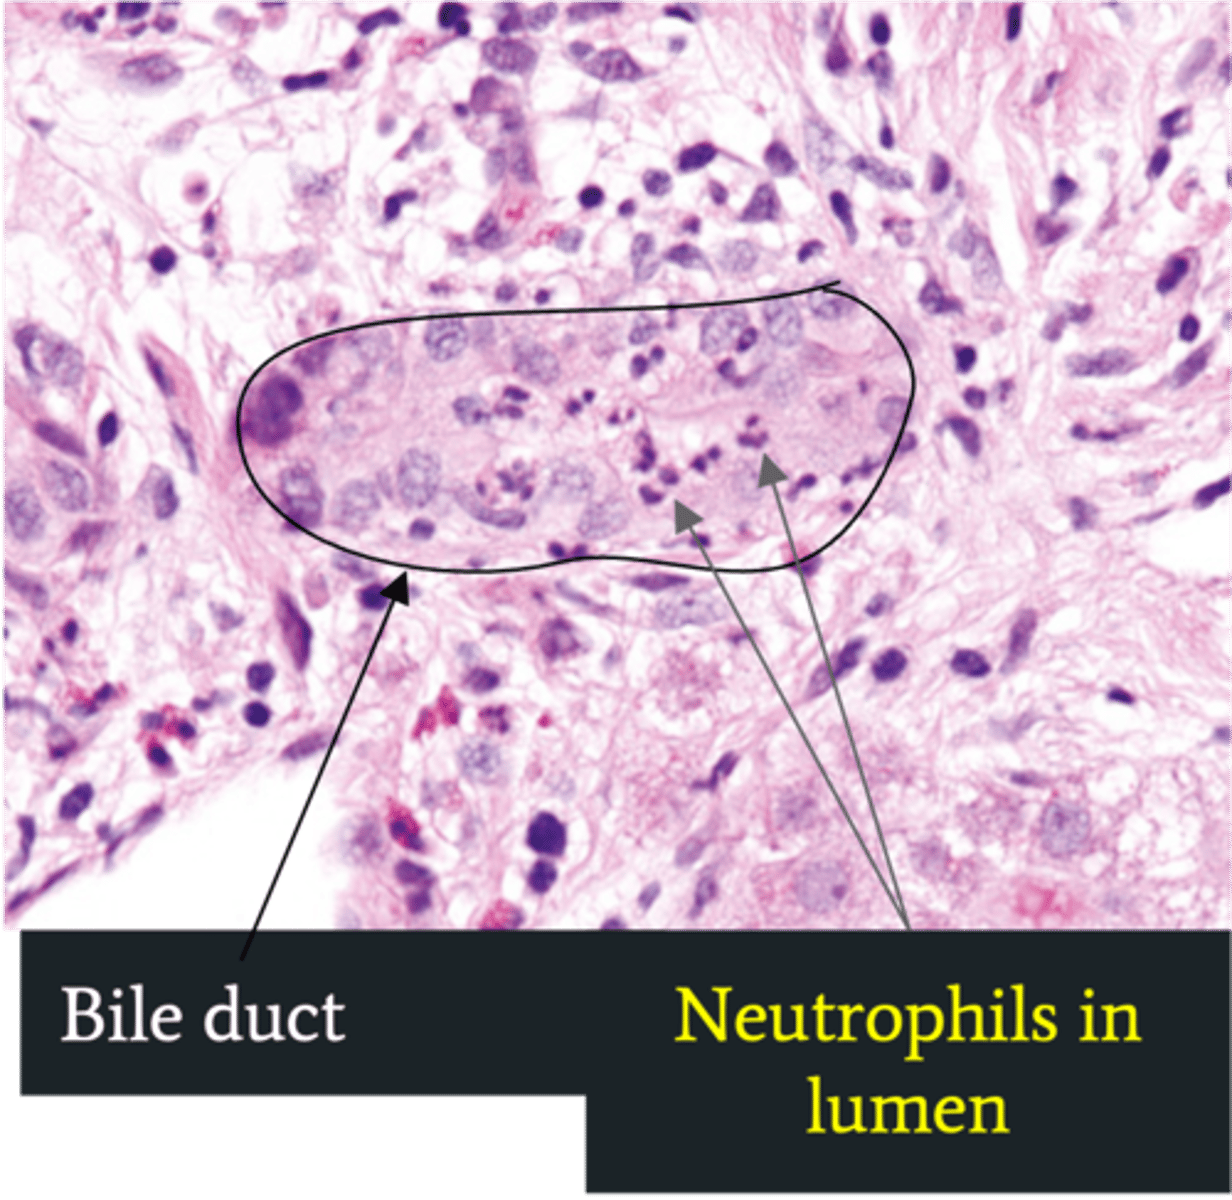

Ascending Cholangitis (Acute Cholangitis)

Define Cholelithiasis Complication:

Infection of bile ducts d/t obstruction leading to stasis/bacterial overgrowth

-Path: Stone blocks flow of bile --> GI bacteria able to ascend biliary tree

-Sx/PE:

> Charcot Triad

>> Jaundice

>> Fever

>> Abd Pain

> Reynolds Pentad (SEPTIC!)

>> Jaundice

>> Fever

>> Abd Pain

>> AMS

>> Shock (Hypotension)

-Dx:

> Labs:

>> Increased WNC

>> Cholestasis = Increased ALP = Increased AST/ALT

>> Increased Tbili & CB

>> Gram (-): E. coli, Klebsiella, Enterobacter

> Biopsy: Neutrophils in bile duct lumen

-Tx:

> Abx

> Biliary Drainage